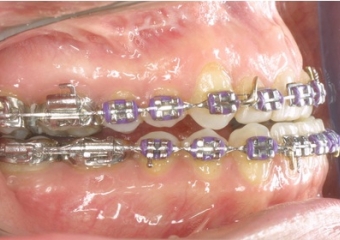

Imagem inicial - Clínica Cliniface

Imagem inicial